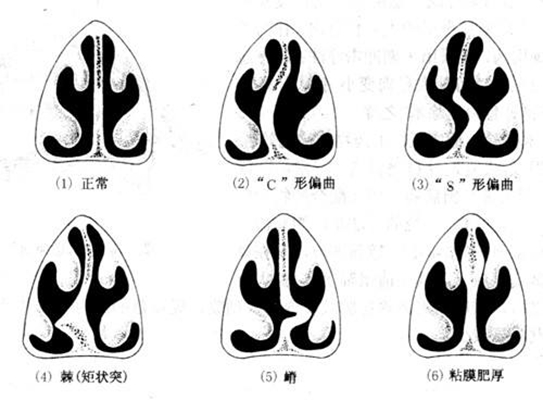

鼻中隔偏曲圖片

鼻中隔彎曲手術圖解 (44)

鼻中隔彎曲手術圖解 (45)

鼻中隔彎曲手術圖解 (46)

鼻中隔彎曲手術圖解 (47)

鼻中隔彎曲手術圖解 (48)

鼻中隔彎曲手術圖解 (49)